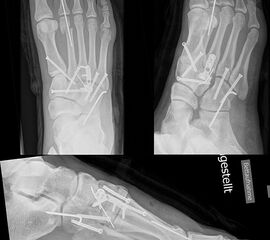

In der Regel werden die physiologisch rigiden TMT-1 bis 3 mittels Schrauben transfixiert. Hierfür werden meist kanülierte Kleinfragment-Kortikalisschrauben (3,5 oder 4 mm) verwendet. Diese können in Stellschraubentechnik von der Metatarsale-1-Basis in das Os cuneiforme mediale (Abb. 17) sowie vom Os cuneifome mediale in die Metatarsale-2-Basis und bei zusätzlicher intercuneiformer Instabilität vom Os cuneifome mediale in das Os cuneifome intermedium eingebracht werden.

Zum Lesen der Bildbeschreibung und zur Vollansicht bitte das Bild anklicken.

Ggf. wird zusätzlich ein K-Draht oder eine Schraube von der Metatarsale-2-Basis in das Os cuneiforme intermedium gebohrt (Abb. 18). Zur Transfixation der TMT-4 und 5-Gelenke werden, entsprechend ihres höheren physiologischen Bewegungsumfangs meist K-Drähte empfohlen. Die Indikation zur Transfixation wird von den meisten Autoren nur bei einer Instabilität gesehen, einige empfehlen eine Transfixation sämtlicher TMT-Gelenke unabhängig vom Ausmaß der Instabilität 10. Kleine, nicht refixierbare Fragmente sollten entfernt werden. Ist ein primärer Hautverschluss nicht möglich, erfolgt die temporäre Weichteildeckung mit Kunsthaut wie Epigard 112951710.